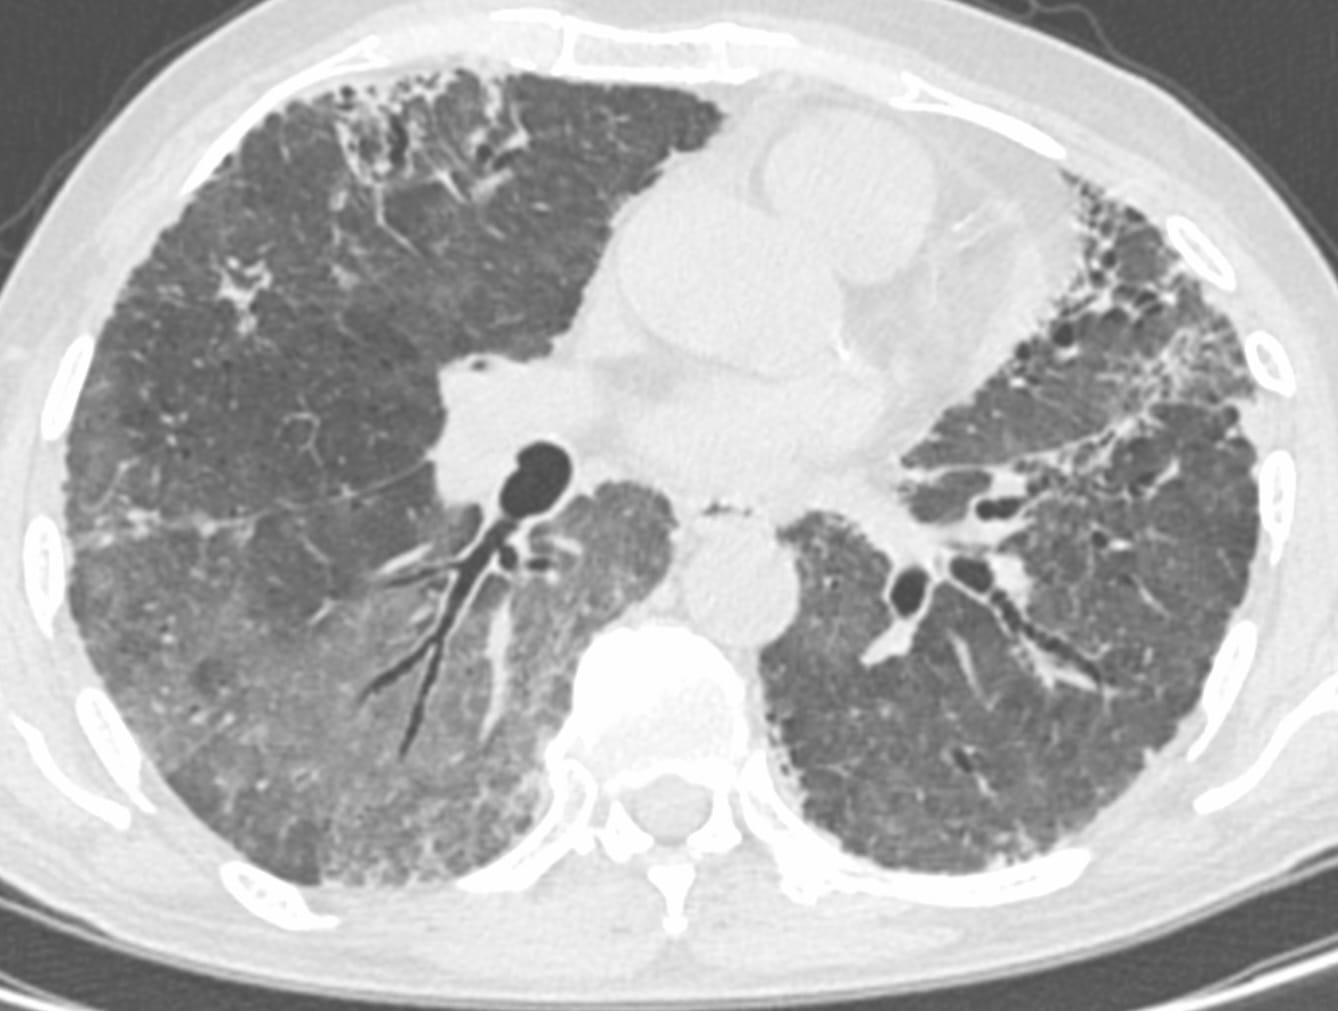

The PDIF sign is basically the presence of a fibrosing ILD typically compacted within the last 2 cm of the peridiaphragmatic lung and may suggest not just CTD-ILD but specifically myositis ILD